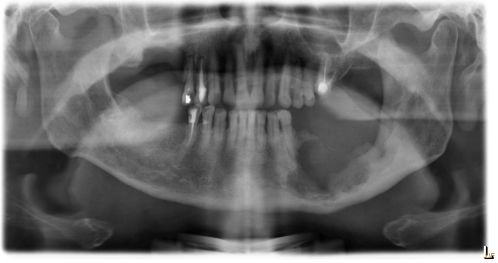

66.64 歲男性長期使用菸酒檳榔,因左下顎臼齒無牙區牙齦腫瘤而來求診,經 X 光檢查如附圖所示,切片檢查 後,病理診斷為鱗狀細胞癌,在口腔癌分期上,此病患最可能為第幾期? (A)第一期 (B)第二期 (C)第三期 (D)第四期